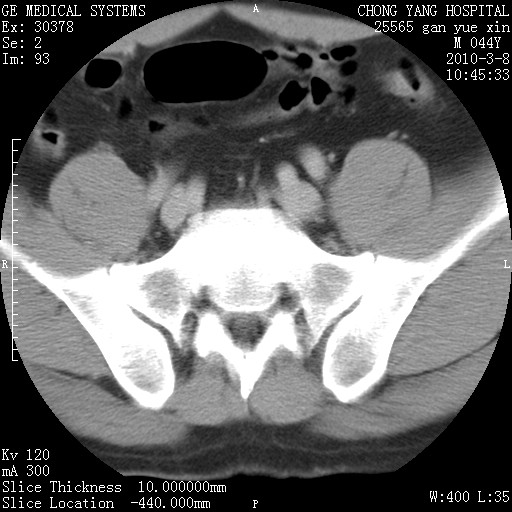

标题: CT24940:主动脉增强,典型病例。 [打印本页]

标题: CT24940:主动脉增强,典型病例。

夹层动脉瘤。

动脉夹层

夹层动脉瘤,典型

主动脉夹层。

动脉夹层的分型:

⒈debakey分型:根据主动脉夹层累及部位,分为三型:ⅰ型:原发破口位于升主动脉或主动脉弓部,夹层累及升主动脉、主动脉弓部、胸主动脉、腹主动脉大部或全部,少数可累及髂动脉。ⅱ型:原发破口位于升主动脉,夹层累及升主动脉,少数可累及部分主动脉弓。ⅲ型:原发破口位于左锁骨下动脉开口远端,根据夹层累及范围又分为ⅲa,ⅲb。ⅲa型:夹层累及胸主动脉。ⅲb型:夹层累及升主动脉、腹主动脉大部或全部。少数可累及髂动脉。

⒉stanford分型:a型:夹层累及升主动脉,无论远端范围如何。b型:夹层累及左锁骨下动脉开口以远的降主动脉。

夹层动脉瘤,少量胸水

夹层动脉瘤;左侧少量胸腔积液。

典型主动脉夹层。